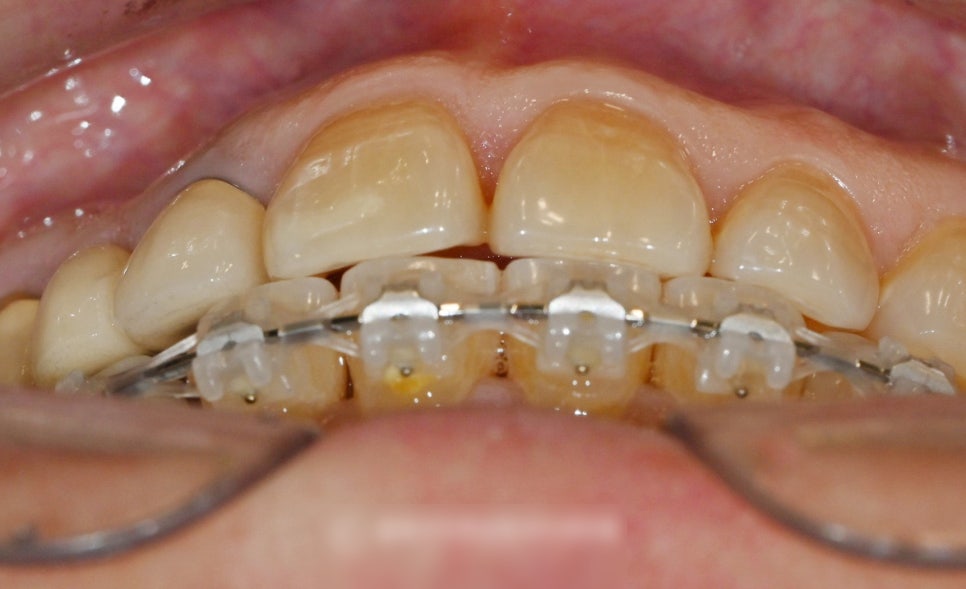

진단이 이뤄졌다면 하악 전치부 6개,

33번부터 43번에 해당하는 치아에

브라켓을 붙이는 과정을 선행합니다.

전체에 브라켓을 붙이는 과정이 아니기에

통증에 대한 부분은 심하지 않을 겁니다.

그러나 브라켓을 붙인 첫날이나

고무줄에 텐션을 준 날에는

조금 불편감이 느껴지실 수 있습니다.

서서히 힘을 주면서 시간을 두고

경과를 지켜보면,

벌어져있던 앞니 공간은 닫힙니다.